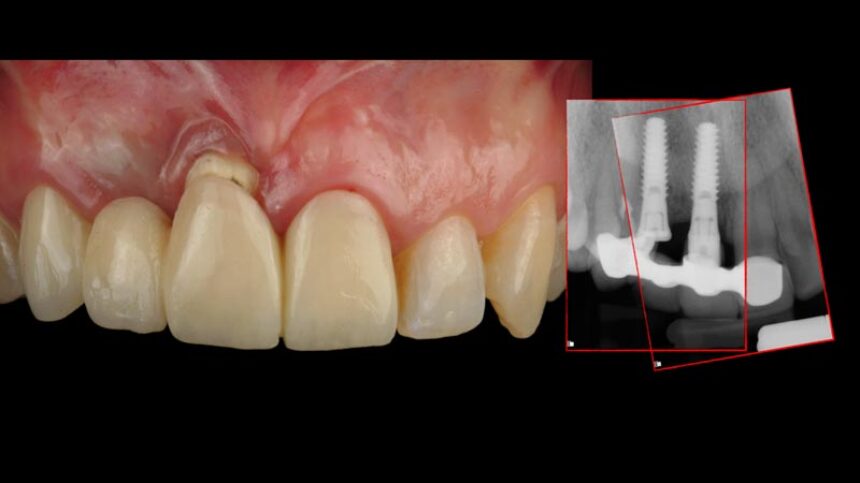

Την διημερίδα θα πλαισιώσει επίσης ο Dr. Iñaki Gamborena εστιάζοντας τις ομιλίες του στους σημαντικούς εκείνους παράγοντες που επηρεάζουν την επιτυχία της θεραπείας στην αισθητική ζώνη τόσο σε ασθενείς με αμιγώς οδοντικό φραγμό, αλλά και εμφυτευματικές αποκαταστάσεις. Οι παρουσιάσεις του θα περιέχουν τη χειρουργική, αλλά και την προσθετική αντιμετώπιση των περιστατικών αυτών και επίσης και αυτός θα επεκταθεί στη διαχείριση πολύπλοκων περιστατικών που έχουν αποτύχει στο παρελθόν.

Διαχείριση των αποτυχιών των εμφυτευμάτων στην αισθητική περιοχή, οι εναλλακτικές.